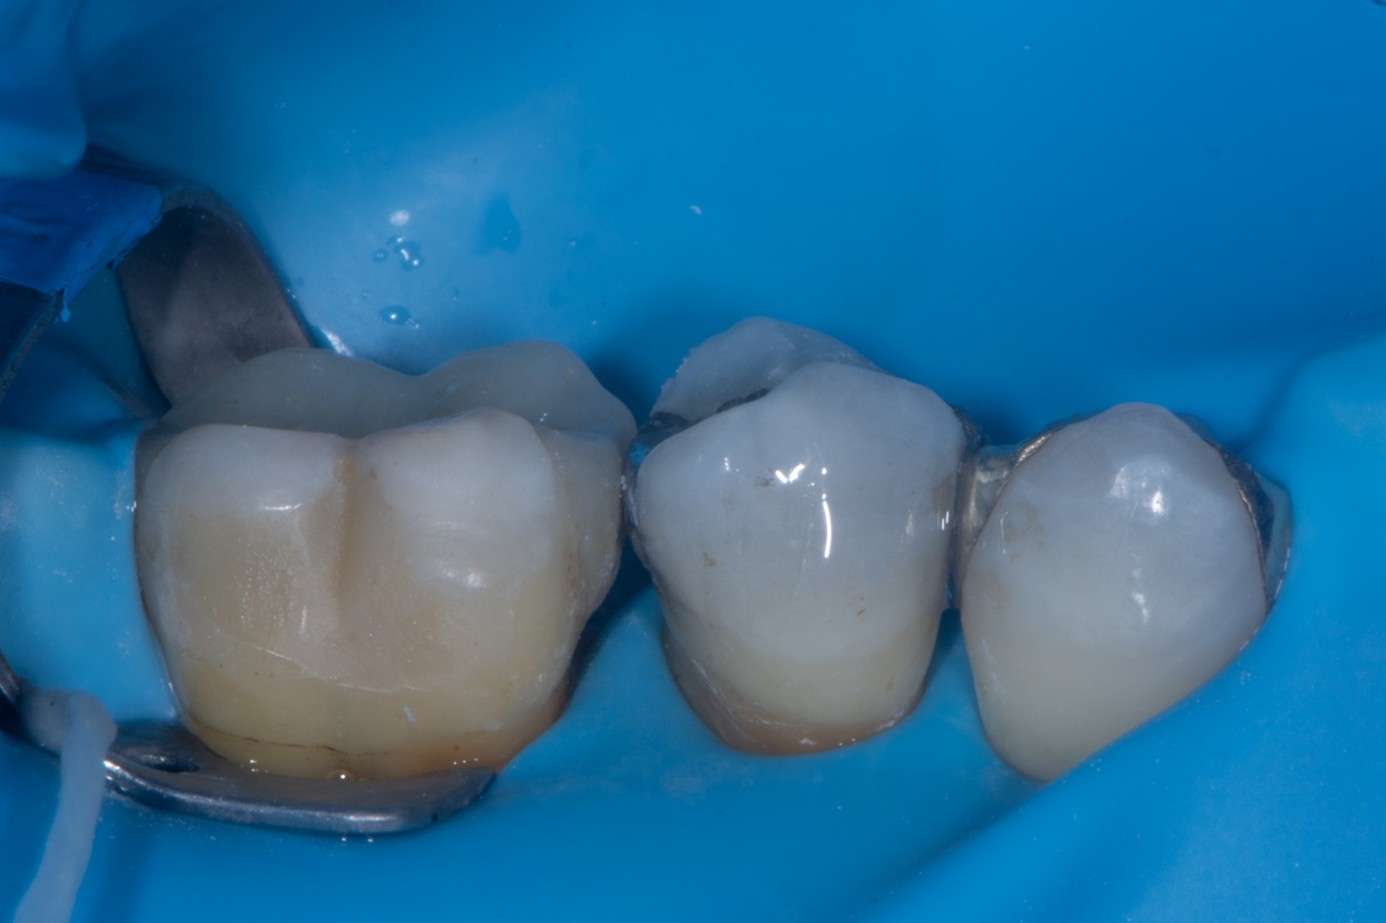

After verifying the fit of the fractured cusp, three-tooth rubber dam isolation was achieved (first premolar to first molar). Dentin adjacent to the fracture line was protected with liquid dam to prevent contamination during amalgam surface preparation (Figure 33). The existing amalgam restoration and fractured surfaces were air-abraded with 27-μm aluminum oxide particles, which effectively cleansed the surface and created micromechanical retention. Care was taken to avoid excessive abrasion of exposed dentin to prevent unnecessary loss of tissue.

(32.) Intraoral view showing a fractured buccal cusp of the mandibular second premolar.

Figure 32

(33.) Amalgam surface prepared for sandblasting to improve mechanical retention. The adjacent dentin is protected with liquid dam to prevent contamination by amalgam particles, which could otherwise cause staining and interfere with hybrid layer formation.

Figure 33